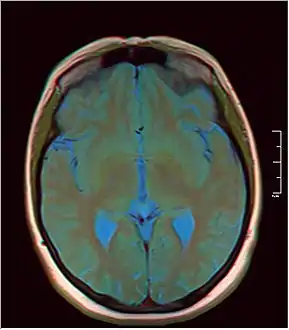

Pineal gland cyst

A pineal gland cyst is a usually benign (non-malignant) cyst in the pineal gland, a small endocrine gland in the brain. Historically, these fluid-filled bodies appeared on 1-4% of magnetic resonance imaging (MRI) brain scans, but were more frequently diagnosed at death, seen in 4-11% of autopsies.[1] A 2007 study by Pu et al. found a frequency of 23% in brain scans (with a mean diameter of 4.3 mm).[1]